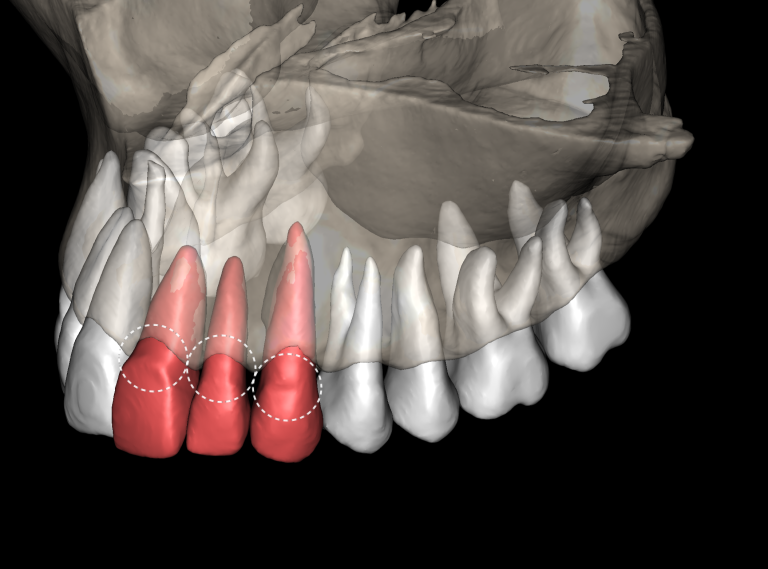

«Эндодонтический отчет» Diagnocat помогает зафиксировать изначальный объем периапикального очага и изучить анатомию и морфологию корневых каналов до начала лечения

Поведено эндодонтическое лечение